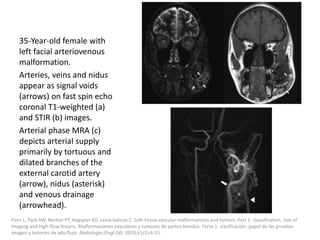

Fever after injection of Picibanil can be treated

with paracetamol.

The positive effect of sclerotherapy is not visible

immediately, but after 4-6 weeks.

Ravindranathan H, Gillis J, Lord DJ. Intensive care experience with sclerotherapy for cervicofacial lymphatic malformations. Pediatr Crit

Care Med 2008; 9: 304–309

Capillary Malformation